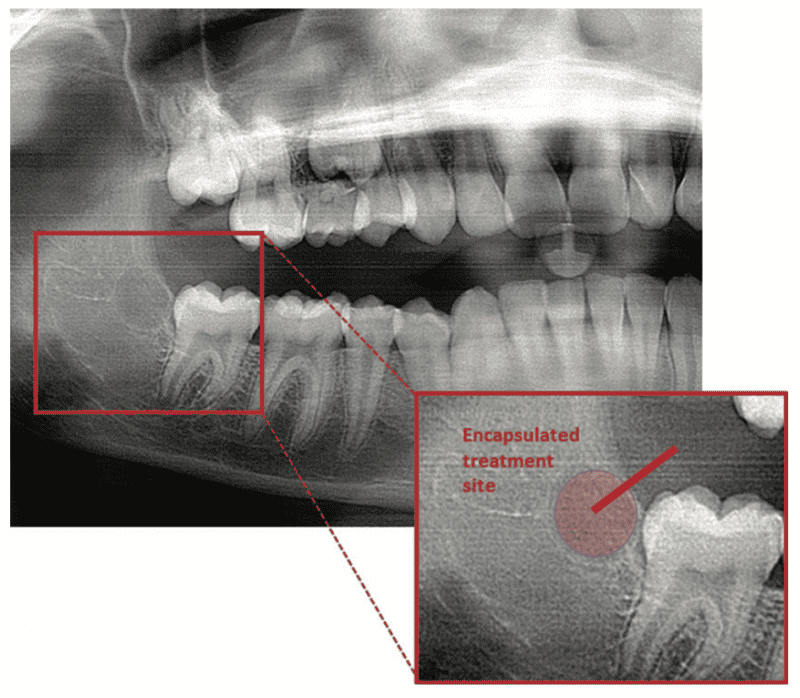

As reported in the April 2023 issue of Journal of Oral and Maxillofacial Surgery, complete molar agenesis was achieved in 100% of TriAgenics’ 3TBA procedures using micro-ablation treatment cycles of 60 seconds or less. Radiographic and histological assessment indicated no presence of treated tooth bud tissue 28 days following 3TBA treatment. Figure 1a shows a typical one-day, pre-operative image of a targeted tooth bud. Figure 1b shows 28-day, post-operative healing results. Histological evaluation at 28-days post 3TBA treatment confirms the presence of complete bony infill with trabecular new bone growth and no detectable viable tooth bud tissue.

Figure 1b. The treated site in Figure 1a (crosshairs) 28 days following 3TBA.